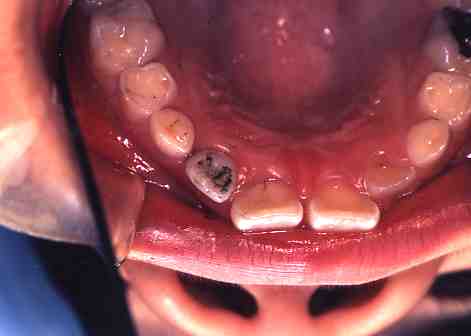

1.術前(ミラー像)

歯の舌面(裏側)が

へこんでいて虫歯に

なりやすい状態です。

2.術中(ミラー像)

歯科用のスミを塗布して

レーザー照射します。